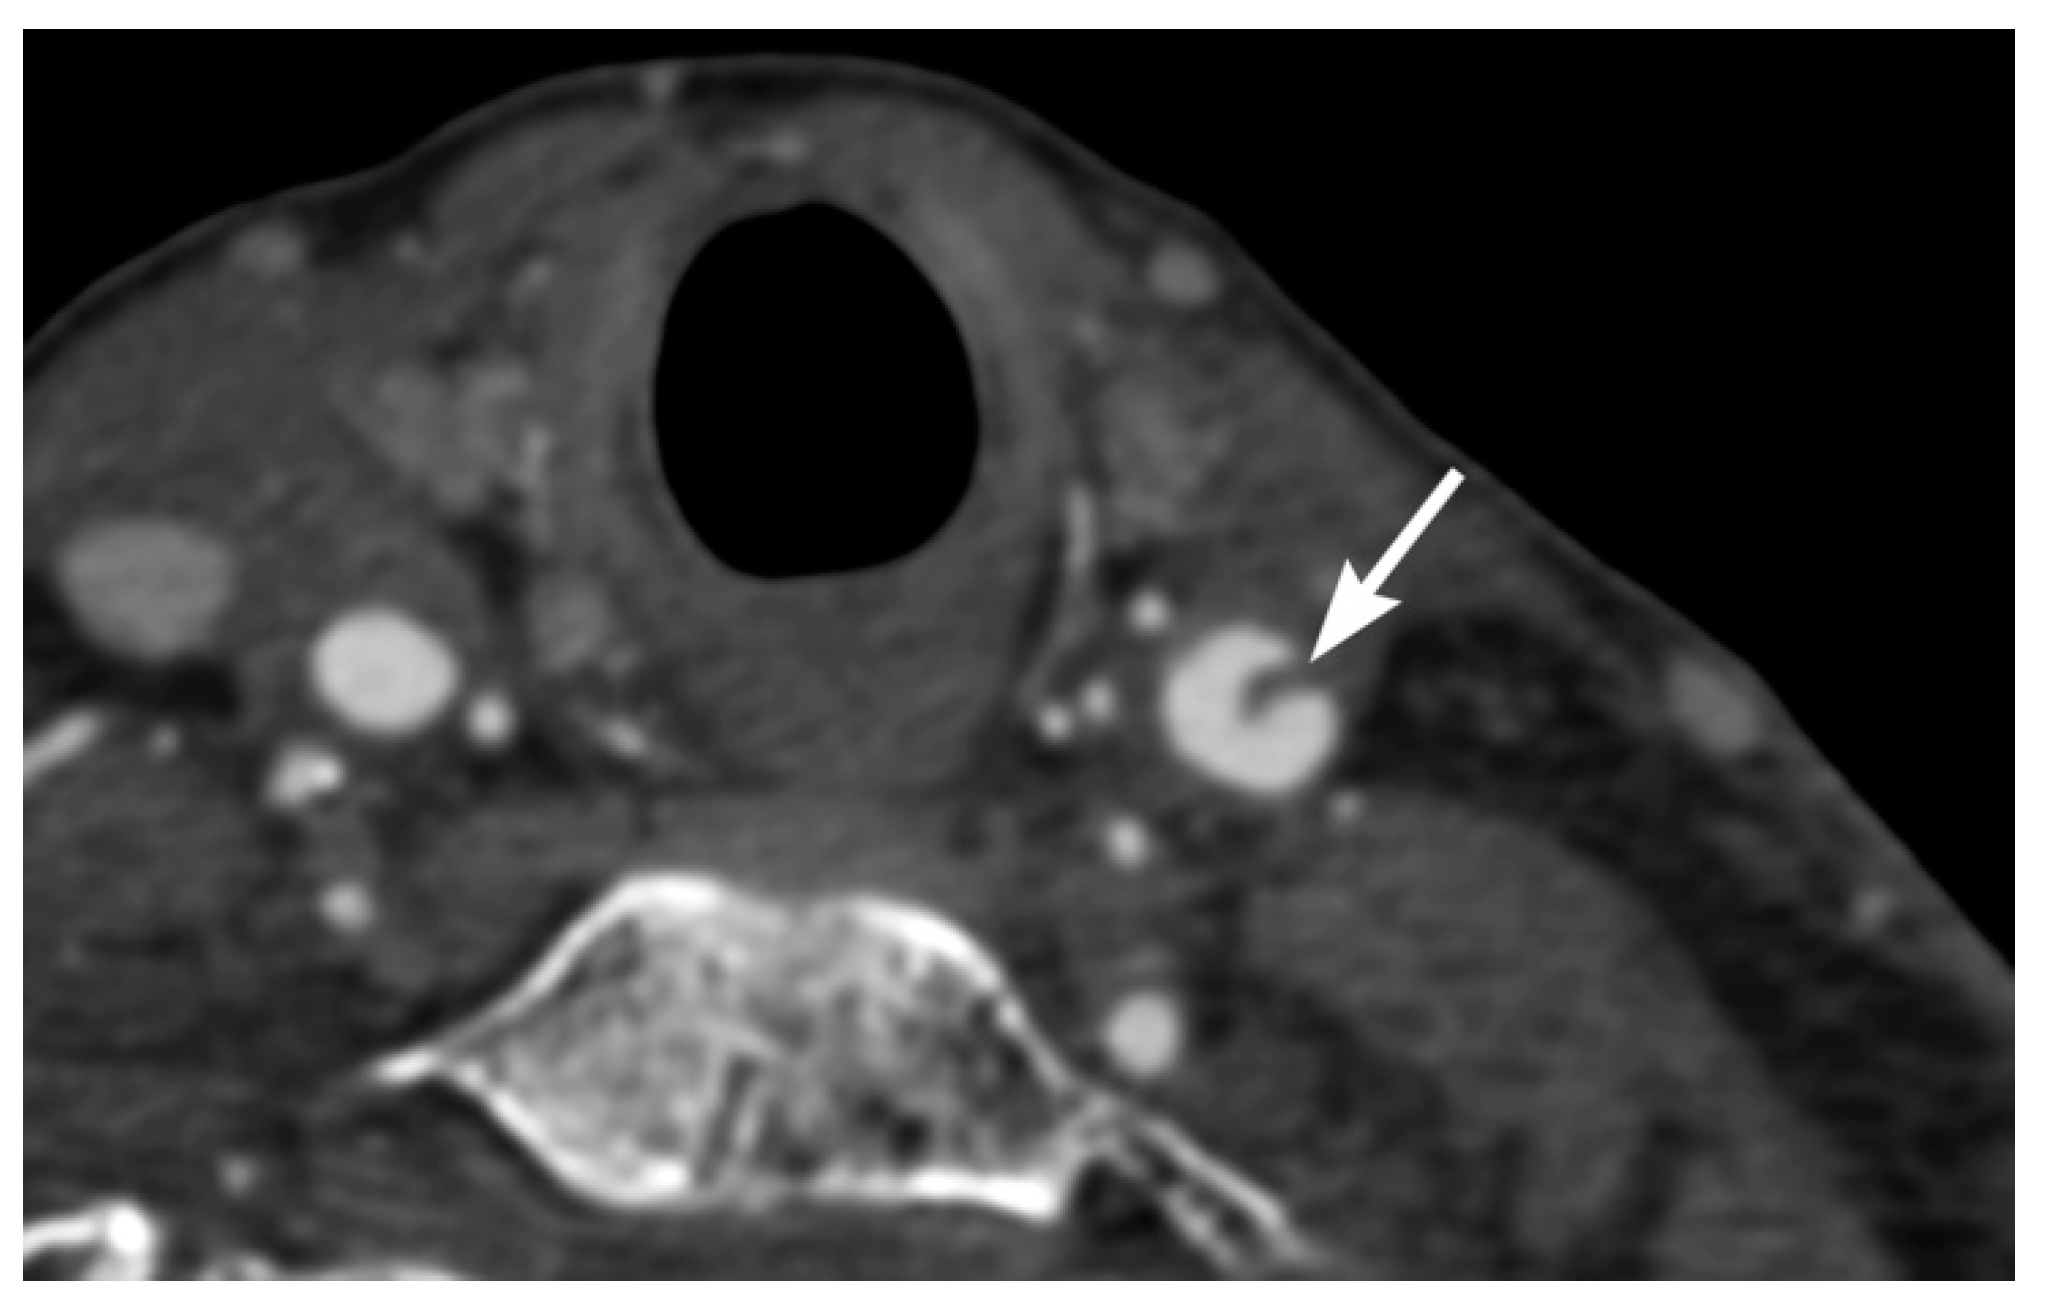

3. Imaging Findings of Arterial Injury